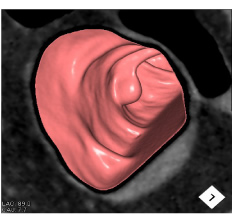

※大腸CT(仮想大腸内視鏡)

大腸CTは、内視鏡を使わない大腸検査です。大腸内視鏡と同様の前処置を行った後に、大腸を炭酸ガスによって拡張させ、新型のマルチスライスCT装置を用いて撮影することで大腸の3次元画像を簡単に得る検査です。

大腸CTは、仮想大腸内視鏡検査とも呼ばれ、内視鏡検査と比較して苦痛や違和感が少なく、短時間で検査可能で受診者の受容性が高いことから、これまで大腸の精密検査に抵抗感のあった方にもおすすめできる検査です。

大腸CT画像

3次元画像(仮想大腸内視鏡画像)